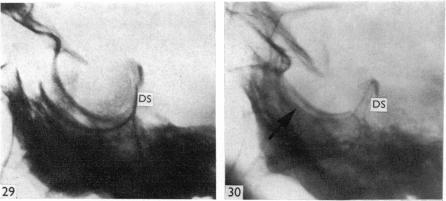

Surgical aspects of the anatomy of the sphenoidal sinuses and the sella turcica.

J Anat. 1977 Dec;124(Pt 3):541-53.